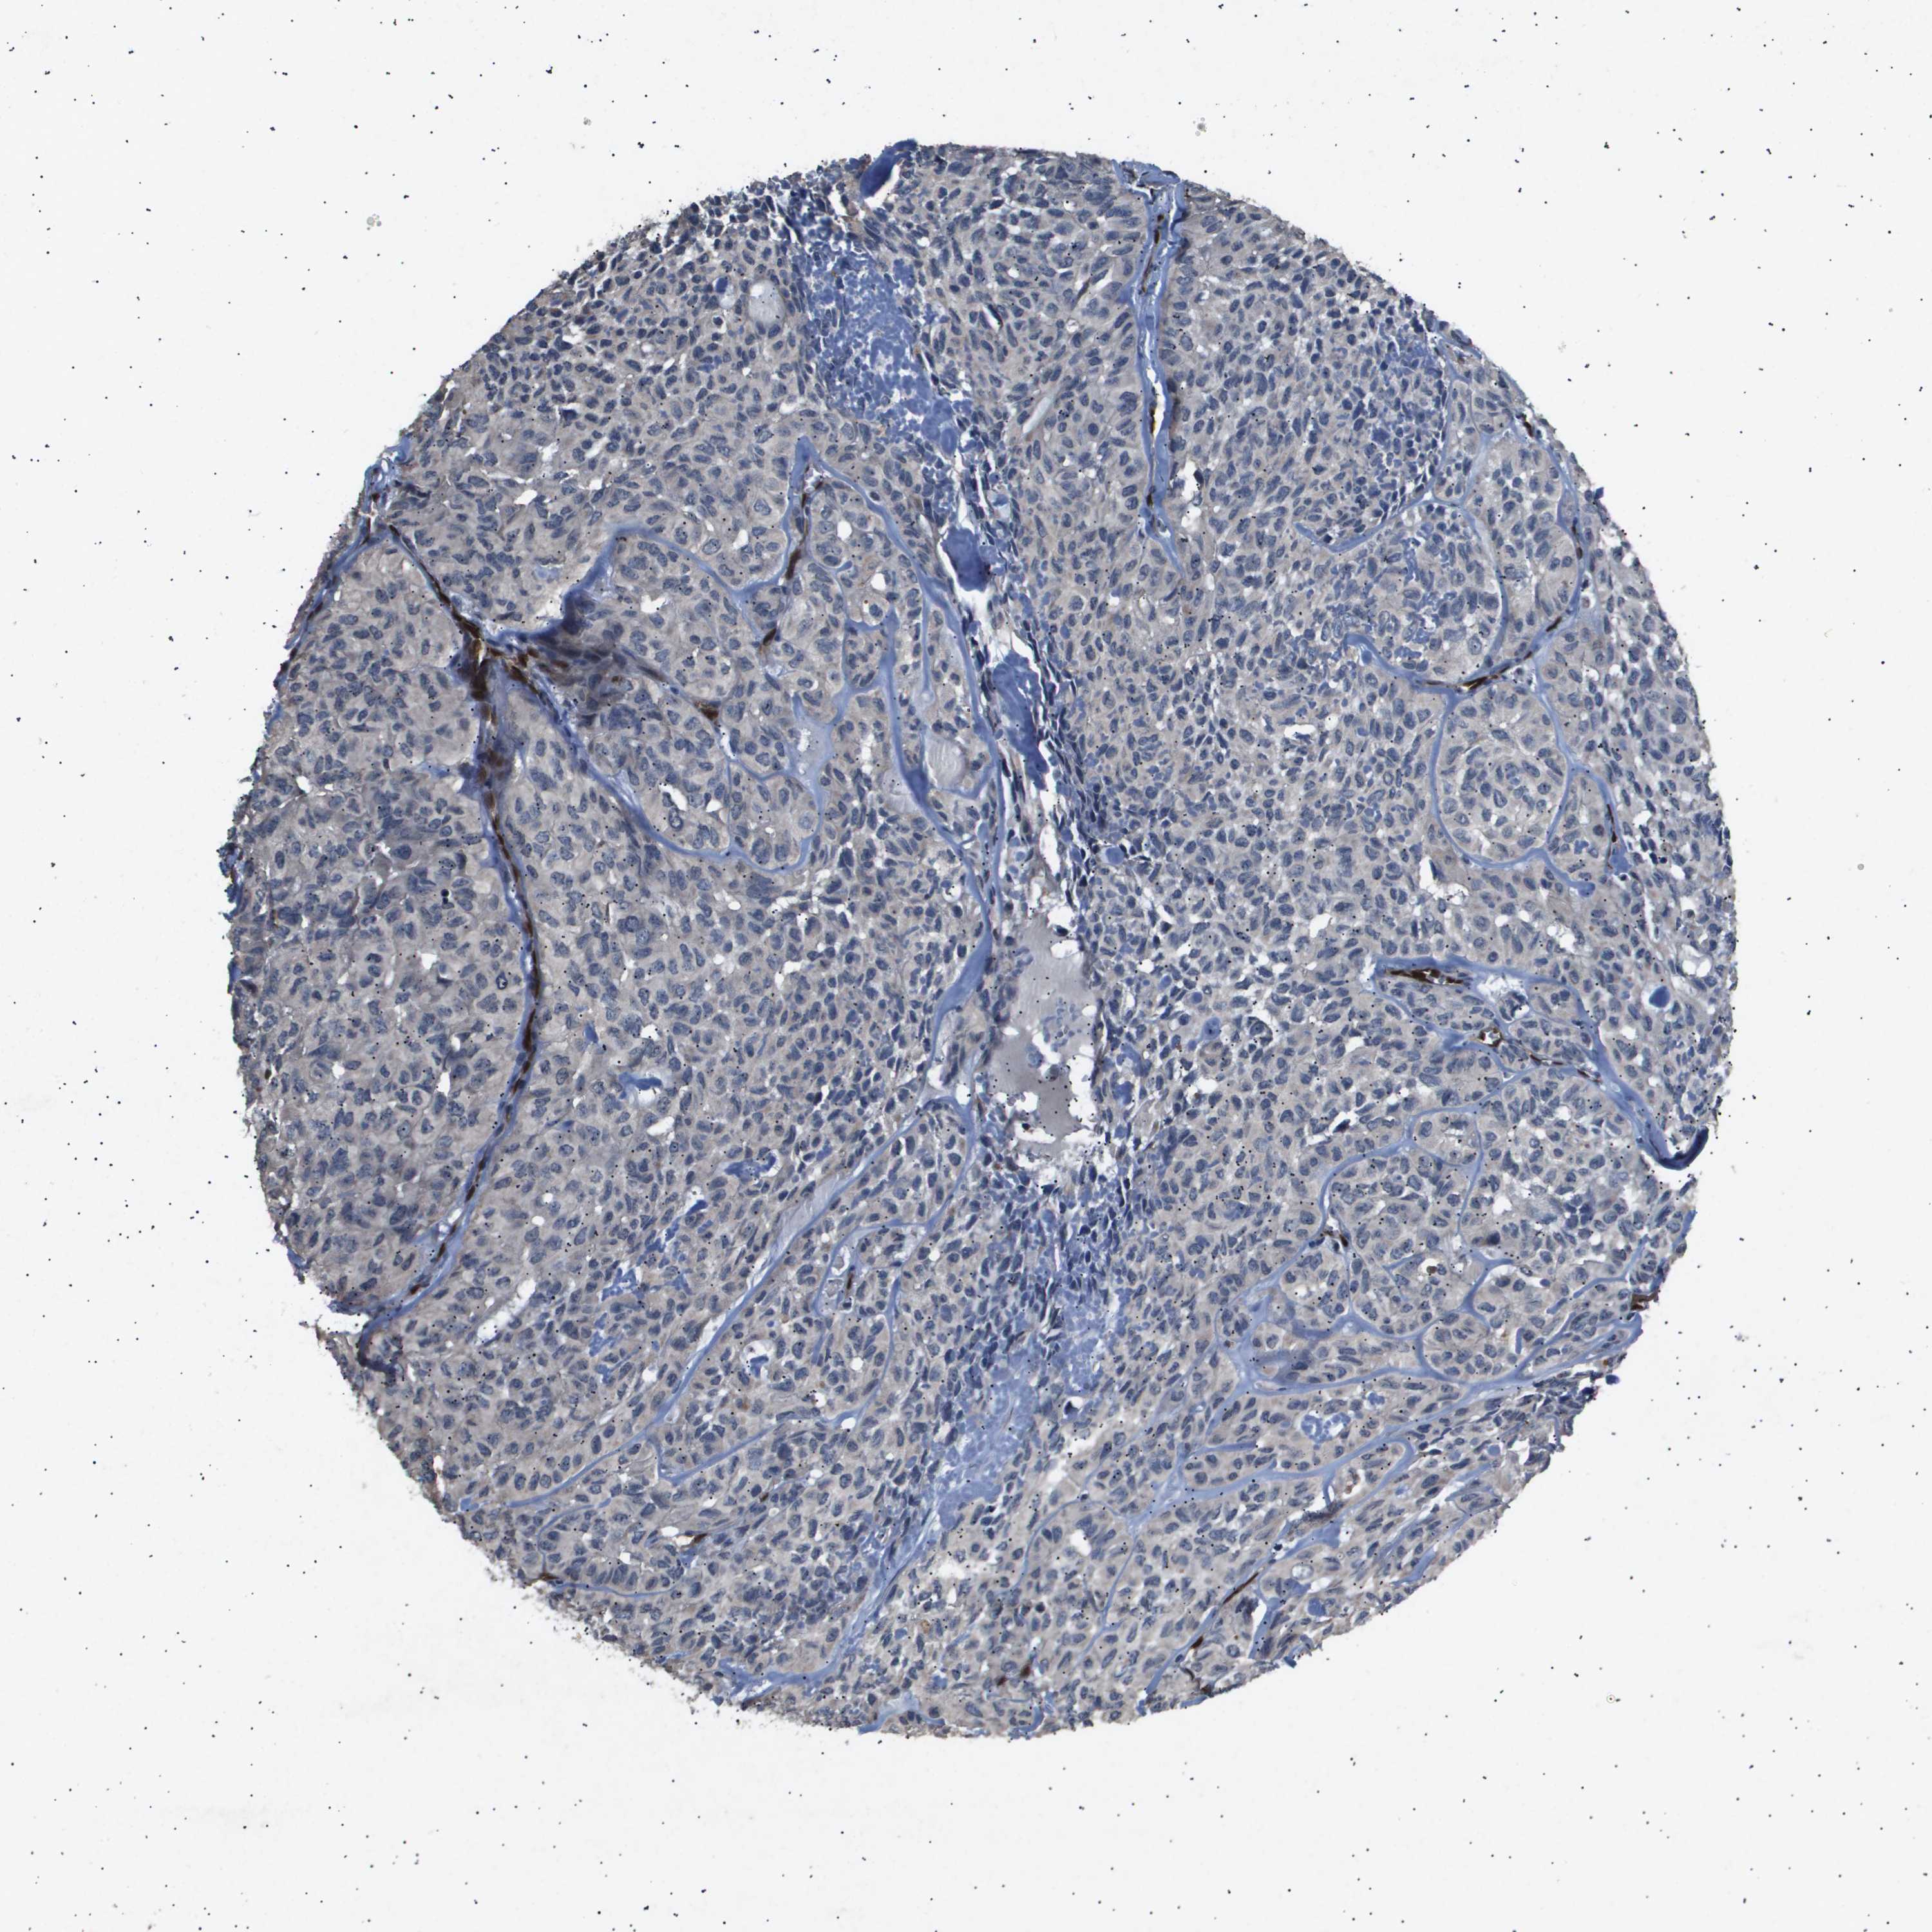

HEAD AND NECK CANCER - Protein expressioni

A mouse-over function shows sample information and annotation data. Click on an image to view it in a full screen mode. Samples can be filtered based on level of antibody staining by selecting one or several of the following categories: high, medium, low and not detected. The assay and annotation is described here.

Antibody stainingi

Antibody staining in the annotated cell types in the current human tissue is reported as not detected, low, medium, or high, based on conventional immunohistochemistry profiling in selected tissues. This score is based on the combination of the staining intensity and fraction of stained cells.

Each image is clickable and will lead to virtual microscopy that enables deeper exploration of all samples and also displays staining intensity scores, fraction scores and subcellular localization as well as patient and tissue information for each sample.

Antibody HPA046598

Antibody CAB018377

Staining

Squamous cell carcinoma, NOS

Adenocarcinoma, NOS

Squamous cell carcinoma, metastatic, NOS